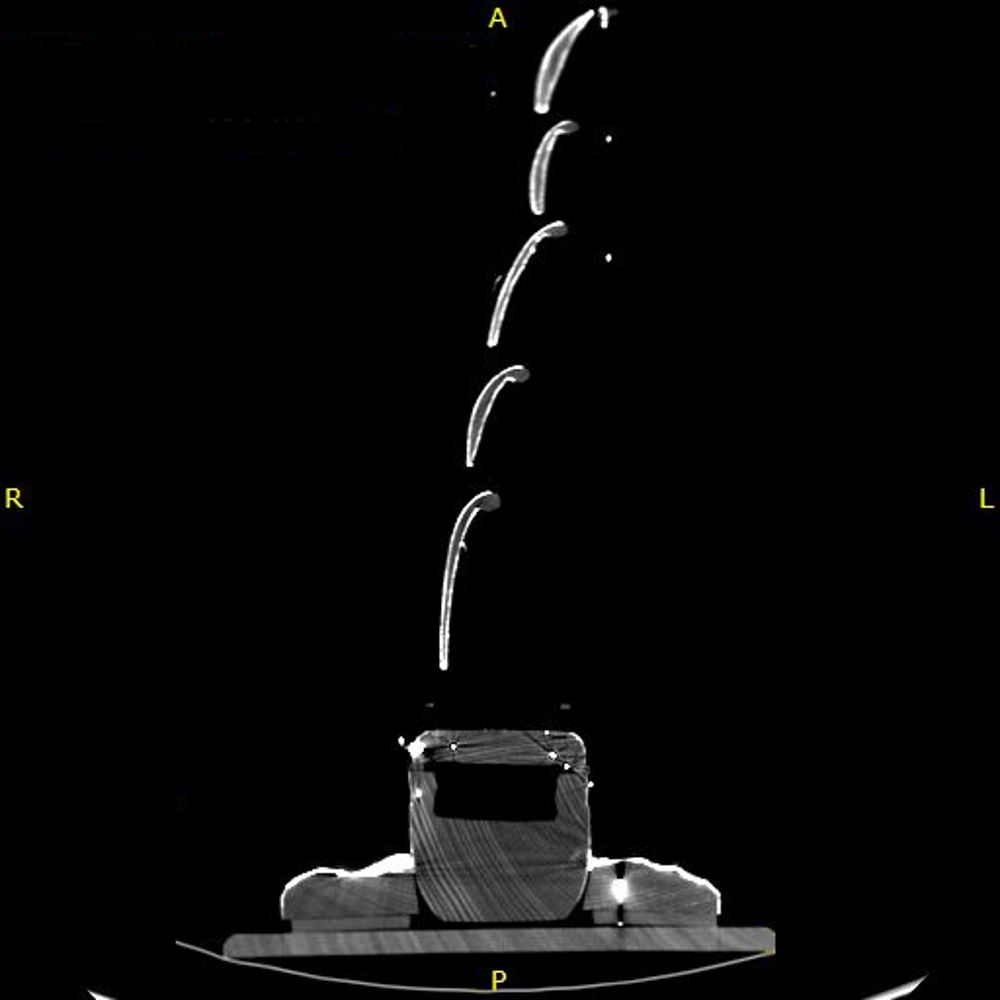

Untersuchung mittels CT und Dokumentation durch verschiedene Zeichnungen

Um einen Vergleich zum vermuteten Vorbild, dem Fünfmastvollschiff 'S.S. PREUSSEN' von 1902, ziehen zu können, wurden detailierte CAD-Zeichnungen angefertigt. Als Grundlage dienten CT-Aufnahmen und Fotografien. Die CT-Untersuchung ergab außerdem einen genauen Aufschluss über die Konstruktion des Modells.